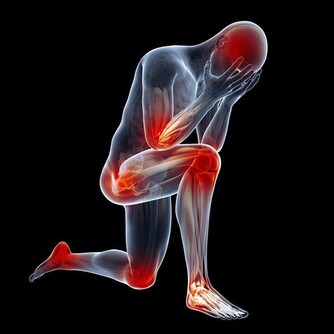

要知道我們是否缺維生素或者微量元素,要看身體出現哪些不正常表現。

身體剛開始缺乏維生素,會出現“體質差”和“抵抗力差”的一些現象,

比如:

乏力,食慾差,瘦弱;

易發生口腔潰瘍,牙齦腫脹;

易感染(細菌、病毒、真菌),

易出現輕度的炎症(感冒、鼻炎、咽炎、扁桃體炎、皮炎等);

容易有低血壓,體溫低,怕冷,四肢冷敏感或冬天四肢冰涼,胃腸道冷敏感,易拉稀;

易出虛汗,肌肉抽筋;等等。

這些不正常的表現在各個人之間或者一個人在不同情況下可以有不同。